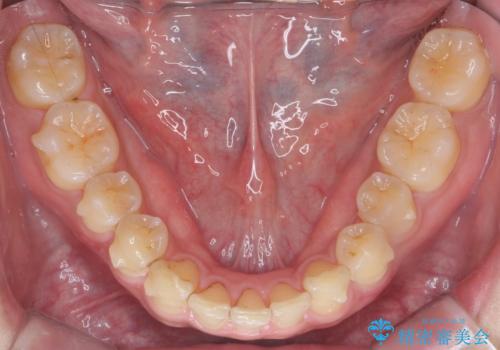

- インビザライン(マウスピース矯正)

- 治療期間

- 11ヶ月

- 前歯のすき間を気にして来院。

前から2番目の歯が小さく厚みがあったため(矮小歯)

矯正治療で1番目の歯を寄せて2番目の歯はセラミックで形をととのえています。